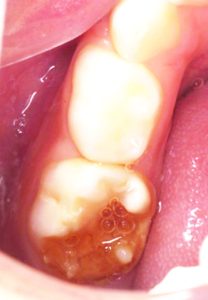

Consider the case of a 5-year-old patient whose lower second milk molar was affected by a condition known as Molar Hypomineralisation. The tooth was filled to address the decay.

The Positive Outcome: Two years later, the permanent molar erupted in its intended position behind the same. This early intervention prevented the decay from impacting the alignment of the permanent teeth. If the milk tooth had not been treated, the space left by the decay could have caused the permanent molar to erupt improperly, potentially leading to future orthodontic issues and the need for braces.